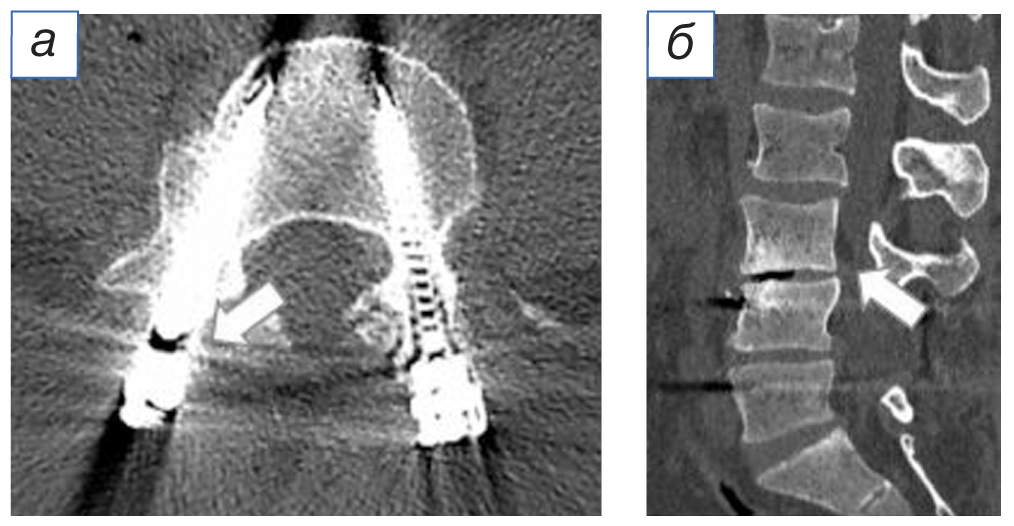

Через 5 лет после операции возобновились боли в области поясницы, правой и левой нижних конечностях, возникла слабость в левой стопе. При контрольном обследовании (рентгенография, мультиспиральная компьютерная томография и магнитно-резонансная томография) поясничного отдела позвоночника выявлены перелом правого верхнего винта системы транспедикулярной фиксации, стенозирование позвоночного канала на уровне LIII–LIV (рис. 1–3).

Рис. 2. Рентгенография: а (боковая проекция) — отмечен перелом транспедикулярного винта на уровне LIV; б (прямая проекция) — указана область перелома транспедикулярного винта на уровне LIV справа.

Fig. 2. Radiography: а (lateral view) — a fracture of the pedicle screw at the LIV level is noted; б (direct projection) — the area of the pedicle screw fracture at the LIV level on the right is indicated.

По результатам мультиспиральной компьютерной томографии: дегенеративно-дистрофические изменения поясничного отдела позвоночника; левосторонний поясничный сколиоз; состояние после оперативного вмешательства, наличие металлоконструкции на уровне LIV–LV, перелом правого верхнего винта.